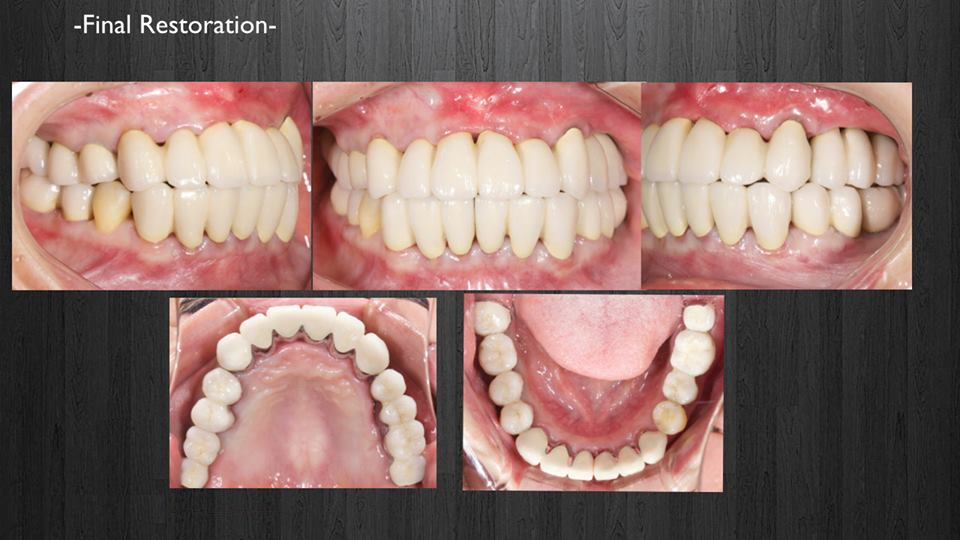

インプラント症例(全顎)

< 症例1 >

- 治療期間:24ヶ月

- 治療回数:126回

- 治療歯数:28歯

- 費用:全顎矯正治療80万円 インプラント治療:155万円 上部セラミック:160万円

- リスク:メンテナンスを怠ると、インプラント周囲炎になる可能性があります。

- インプラント手術には合併症が伴う場合があります。

- 治療期間は治癒の状態により前後する場合があります。